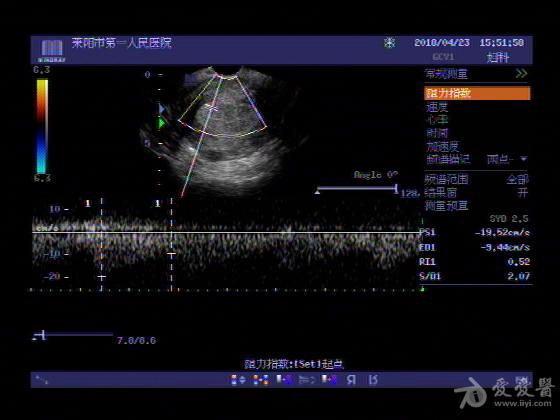

女,48岁,月经量多,两个月,一年前出现过类似现象,刮宫吃药后缓解。

超声可见:子宫内膜显著增厚,后肌壁内膜可见范围约3.27X0.90CM低回声区,CDFI显示较丰富线样血流,宫底宫腔内见类**状低回声结节。前肌壁见多发类圆形低回声结节。

超声提示:子宫内膜增厚(建议刮宫病理),子宫多发肌瘤

病理结果:内膜增生